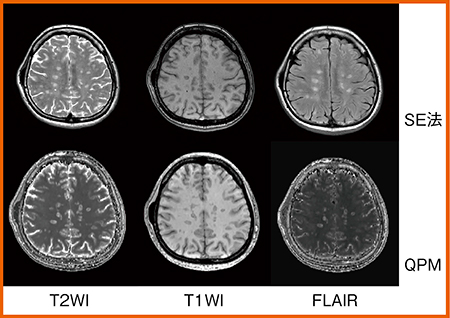

本症例について,QPMによるほかの定性画像をSE法の画像と比較した(図2)。QPMでは,3Dで一度に撮像するため多少解像度が低下するが,SE法と同様のコントラスト画像を得られることがわかる。

図2 症例1:SE法とQPM定性画像